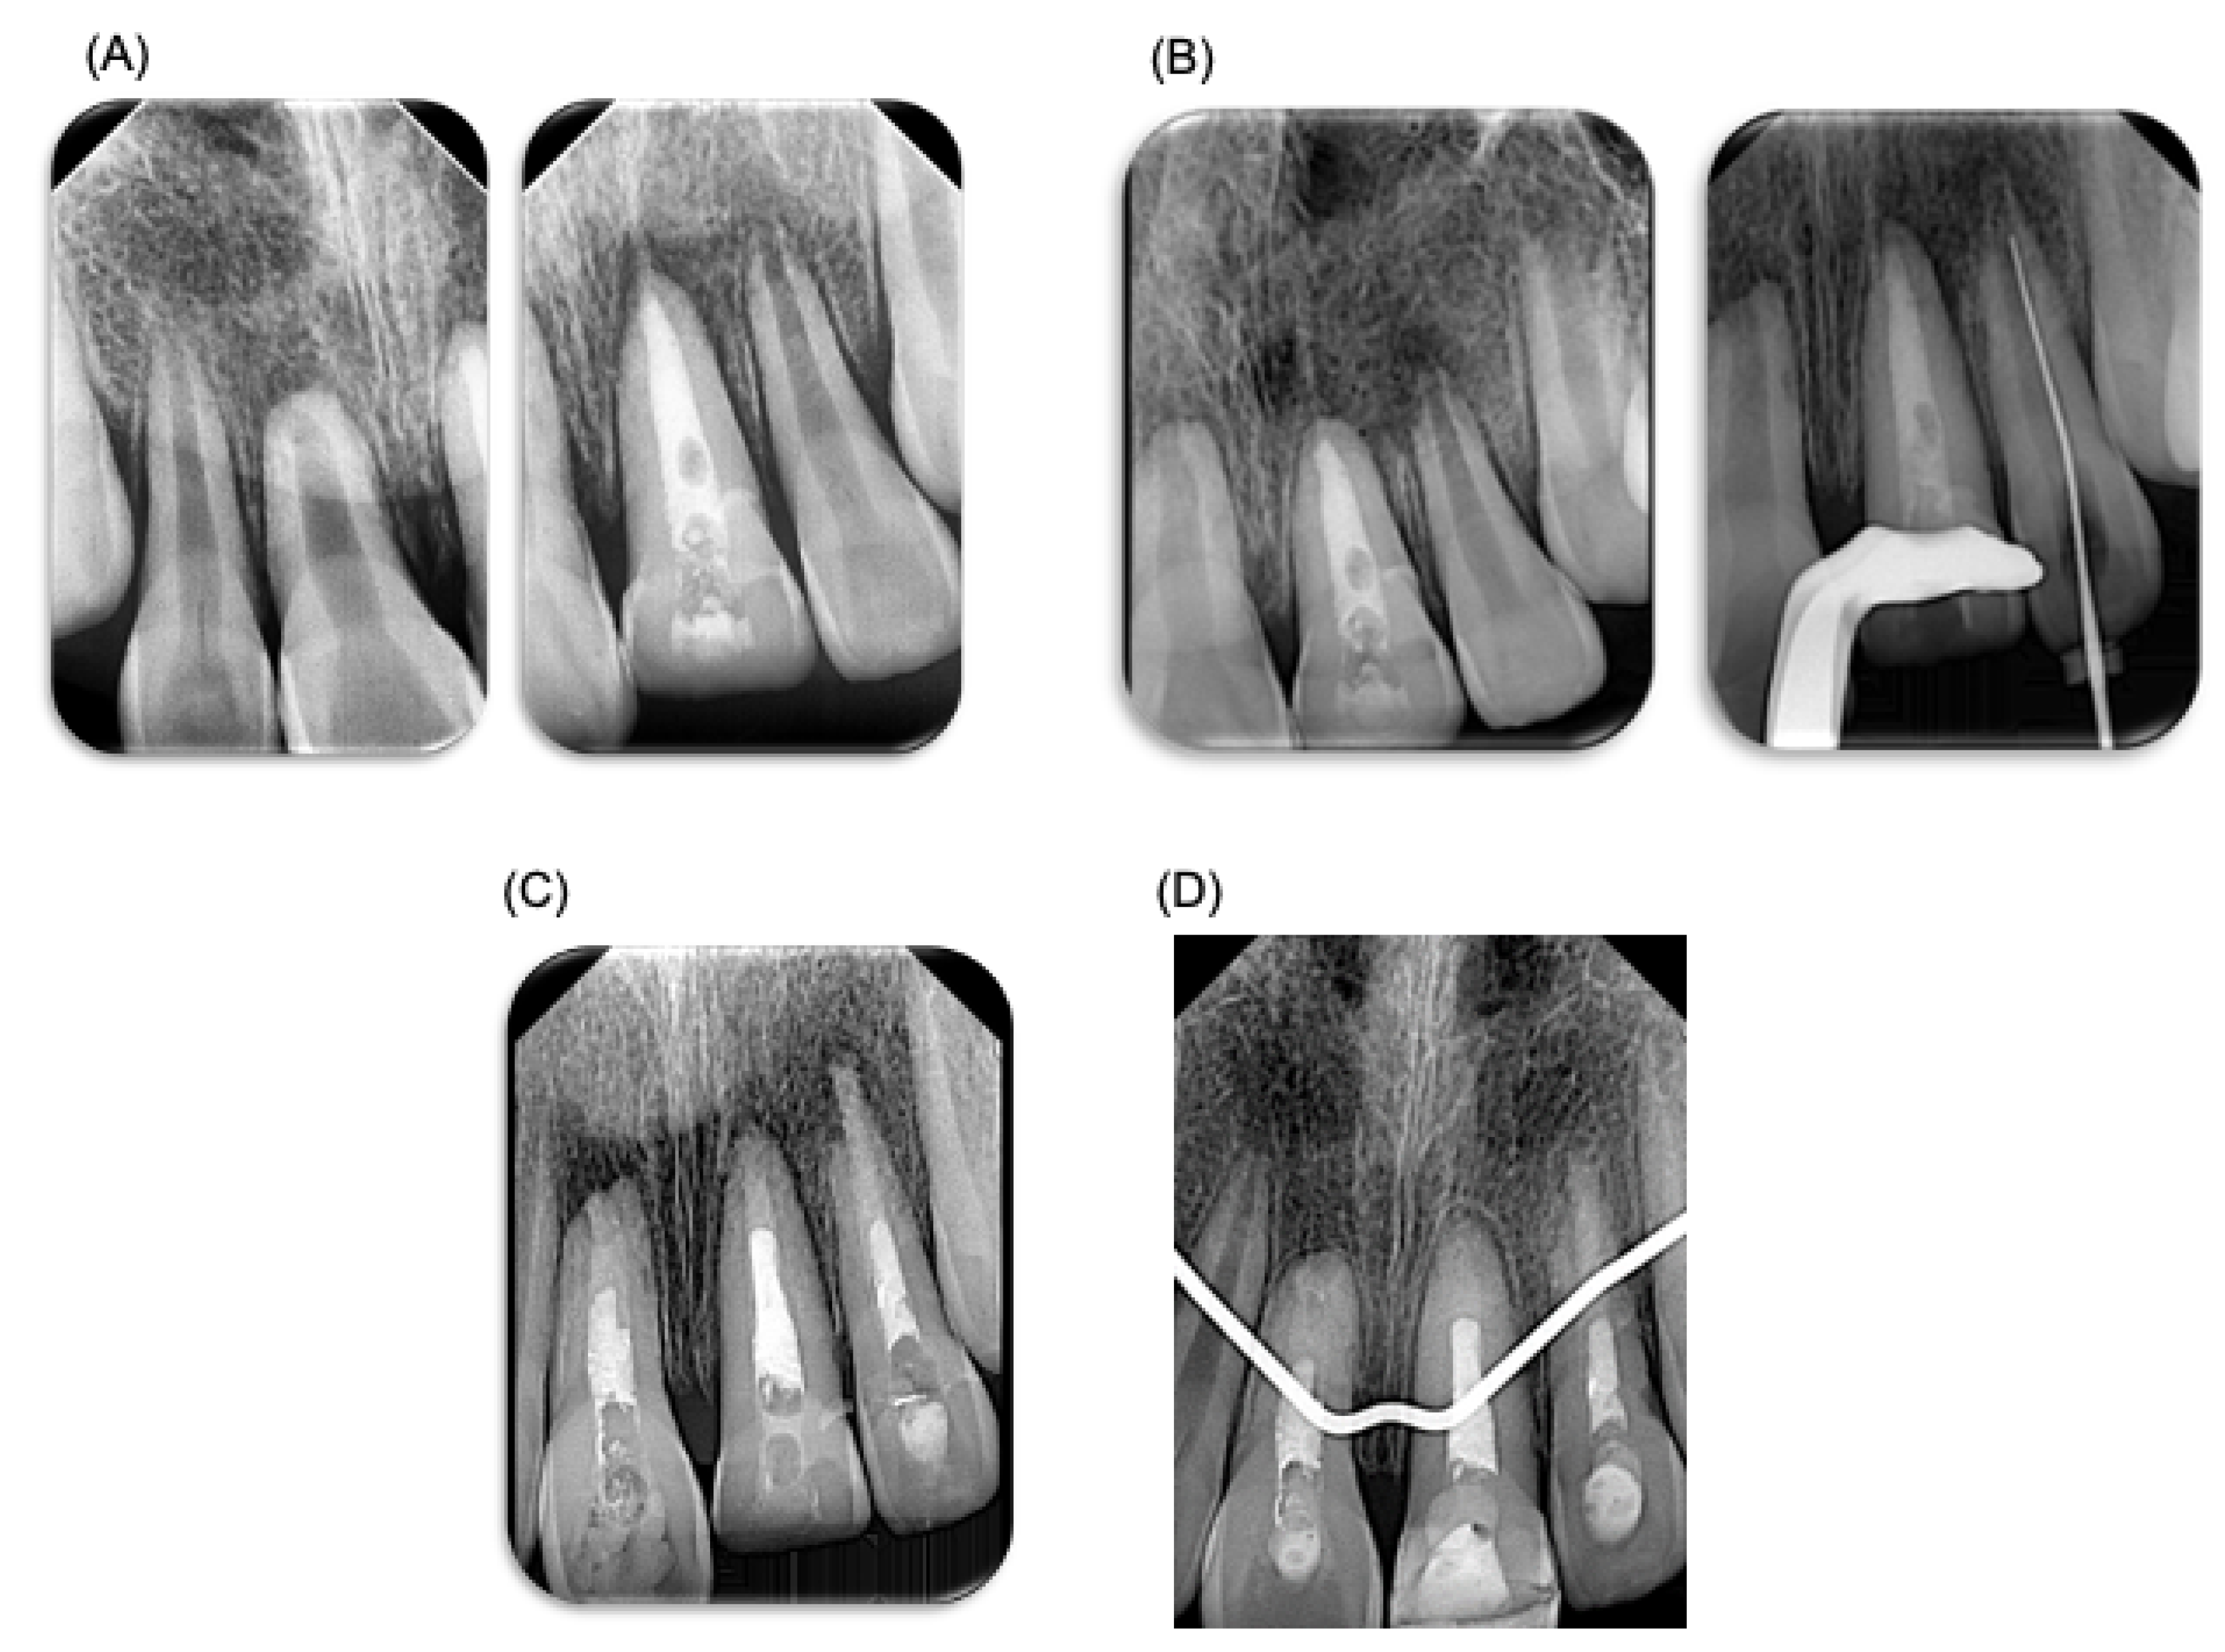

Figure 3.

Endodontic treatment. Endodontic treatment performed on patient. (A) X-ray prior to endodontic treatment performed. (B) Control X-ray, 3 weeks after endodontic treatment, where root resorption can be observed. (C) X-ray after the performed endodontic treatment. (D) X-ray at 3 months, where the apical closure of teeth can be observed (teeth 11 and 21). A BiodentineTM plug was placed. This material has a different radio-opacity than gutta-percha material; therefore, in the X-ray it may look like the endodontic treatment was not performed fully.

A week later, the patient visited the endodontist for evaluation and diagnostic tests, revealing pulp necrosis in tooth 21. Root canal treatment was performed under local anesthesia using mepivacaine 2% with epinephrine 1:100,000 of anterior dental and nasopalatine nerves (Zeyco, Zapopan, Jalisco, Mexico). Absolute isolation was achieved for the access cavity, and odontometry was performed with a K25 file to 19 mm. Protaper Gold rotary systems and K-Files up to a size 90 file were used. The irrigation protocol included 2.25% NaOCl, followed by final irrigation with sonic activation using NaOCl, saline solution, and 17% EDTA (by using three rechanges during 20 s each solution). Root canals were dried with sterile paper points. Intracanal calcium hydroxide medication mixed with water basis was placed, and a temporary restoration with ProRoot (Cavit, 3M ESPE, Seefeld, Germany) was applied (Figure 3). Three weeks after endodontic treatment, tooth 21 was asymptomatic. However, tooth 22 exhibited grade 3 mobility despite being negative on palpation and percussion. In addition, radiographic examination revealed external root resorption in the apical third of tooth 22; therefore, endodontic treatment was performed on tooth 22, carried out following the same specifications. Three weeks later, the temporary filling in tooth 21 was removed (Figure 3). Root canal treatment was also carried out on tooth 11, and endodontic treatment was carried out following the same specifications. Because the teeth had open apices, a biodentineTM (Septodont, Saint-Maur-des-Fossés Cedex, Paris, France) plug was placed for apical sealing.